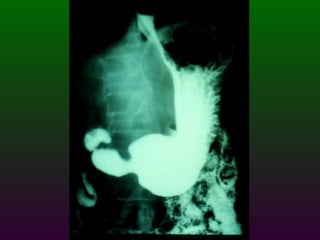

S.E.G.D.  Serie esófago gastro duodenal Definición  Estudio de doble contraste (bario) y aire del tracto digestivo superior. (esófago, estómago, duodeno)

SEGD. VALORACIÓN: Tamaño Longitud  Capacidad de distensión (calibre) Llenado Vaciamiento Patrón: Mucosa

SEGD La impresión radiológica básicamente se divide en tres limitados y un difuso Ulceración Estrechez Masa Compromiso difuso por ulceración y/o engrosamiento  parietal

SEGD ENFERMEDADES DEL ESTÓMAGO Y DUODENO DIVISIÓN ANATÓMICA DEL ESTÒMAGO CARDIAS  FONDO CUERPO  ANTRO  PÍLORO